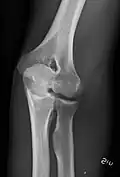

- Knee - AP and Lateral. Intra Condular projections on request

- Patella - Skyline projection

-

Right knee, anteroposterior -

Right knee, lateral -

Patella, (slightly skew) skyline